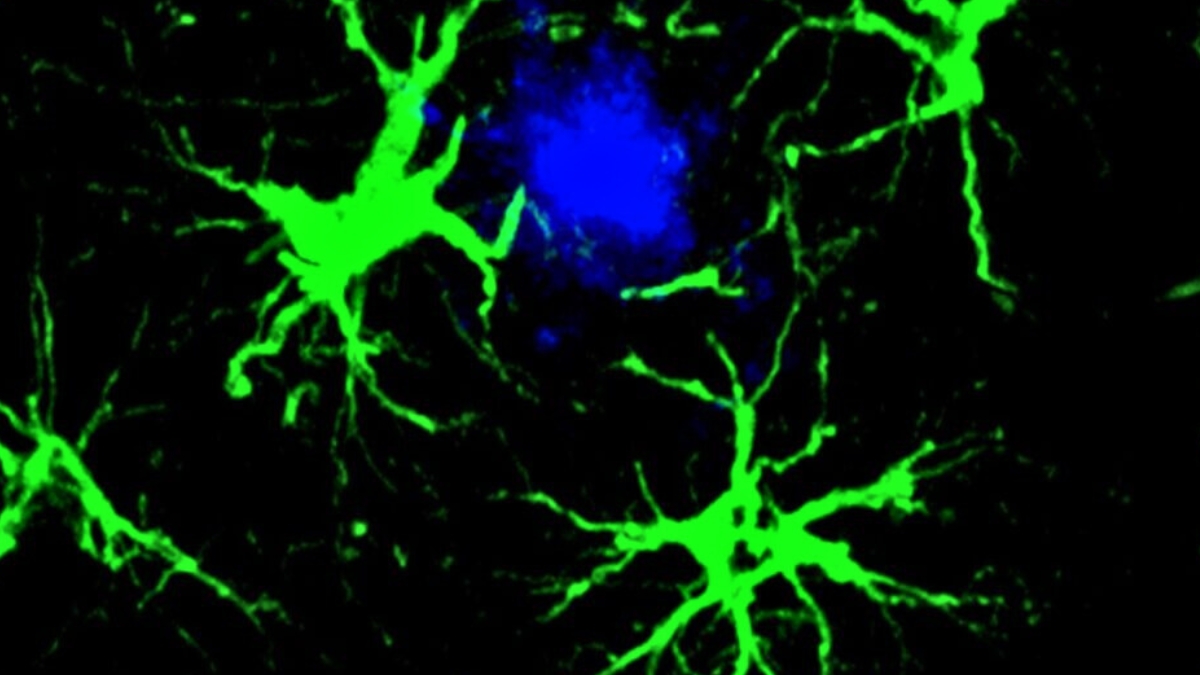

Šiame tyrime mokslininkai sutelkė dėmesį į žvaigždiškos formos smegenų ląsteles – astrocitus. Jie buvo genetiškai modifikuoti taip, kad atpažintų ir šalintų su kognityviniu nuosmukiu bei Alzheimerio liga siejamus amiloido beta baltymus.

Įprastai astrocitai atlieka daug svarbių užduočių smegenyse, įskaitant „tvarkdarių“ funkcijas. Ši technologija leidžia sutelkti jų bendrą galią ir nukreipti ją prieš amiloido beta baltymus.

Gavę naują „užduotį“, astrocitai tampa itin susitelkę į amiloido beta apnašų šalinimą ir tai atlieka labai efektyviai.